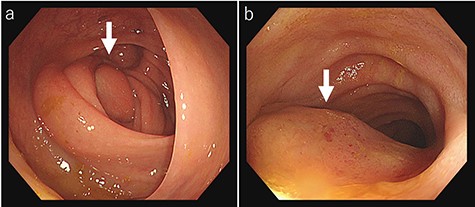

Laboratory tests revealed that her white blood cell count and carcinoembryonic antigen (CEA) levels were within normal limits (8600/μl and 2.4 ng/ml, respectively). However, C-reactive protein and carbohydrate antigen 19–9 (CA 19–9) levels were elevated (17.73 mg/dl and 87.8 U/ml, respectively). Colonoscopy showed swelling of the Bauhin valve and an elevated tumor of the terminal ileum (Fig. 1), but the biopsy specimen showed no malignancy. Abdominal contrast-enhanced CT detected a partially high-density tumor (diameter: 90 × 70 mm) in the cecum with some peripheral lymphadenopathy (Fig. 2). Magnetic resonance imaging (MRI) revealed a tumor (diameter: 60 × 40 mm) with thickening of the appendix wall near the cecum (Fig. 3). Although her pain resolved with conservative therapy, we diagnosed as suspected cecal cancer based on the imaging findings and elevated tumor marker levels.

Colonoscopy findings colonoscopy reveals swelling of the Bauhin valve (a) and an elevated tumor of the terminal ileum (b).